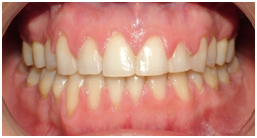

A UB orthodontist has documented that "playing" with a pierced-tongue stud can eventually result in a gap between the front teeth.

In many cases, patients did not have a space between their front teeth prior to the tongue piercing.

Subjects frequently develop a habit of pushing the metal stud in their tongues up against and between the front teeth, creating a gap.

Thousands of dollars of orthodontia may be required to close the gap, as was the case with this patient.

The patient provided the research team with photos that demonstrated she had no diastema, or space, prior to having her tongue pierced. For the purposes of treating this patient's space, it was assumed that positioning of the tongue stud between the maxillary central incisors or "playing" caused the midline space.